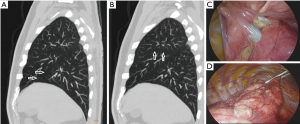

The mean accuracy of the prediction of complete fissures through the evaluation of MDCT scans by radiologists varied between 76.81% for the left posterior oblique portion and 85.06% for the left anterior oblique portion. The mean accuracy for RH fissure, usually the most frequently incomplete and most difficult to define precisely, was 80.62%, varying slightly between the three radiologists, from 74.42% (radiologist C) to 83.72% (radiologists A and B). Positive predictive values were higher for LOA fissure (94.45%) and lower for RH fissure (70.83%). Radiologist A, the most experienced, achieved a higher accuracy among radiologists. Sensitivity, specificity, positive and negative predictive values, and accuracies are shown in Table 2 and Figure 1. We demonstrate two examples of fissures visualized in the surgery and in the MDCT (Figures 2,3).

The fissure evaluation by MDCT scans is considered to be quite accurate, but little is known if these findings closely correspond to the anatomical categorization by direct inspection. In our study, we found a very good accuracy of all radiologists in the fissure assessment compared to the intra-operative findings in lung surgeries. Overall accuracy rates around 80% and reaching 85% for LOA portion are important for daily clinical decisions. Even for RH fissure, considered the most difficult to assume as complete and with lower accuracy of MDCT scans analysis (16), we found a high accuracy (80.6%) of this evaluation. Sensitivity was higher for RO fissures (85% for ROP and 95% for ROA fissure), and the positive predictive value was higher for LOA fissure (94%). The division of oblique fissures in two halves is critical, for example, for the right side, considering that upper lobe is bordered by posterior half of oblique fissure and horizontal fissure. Thus, although the anterior half is incomplete, this will not affect the CV of the upper lobe.